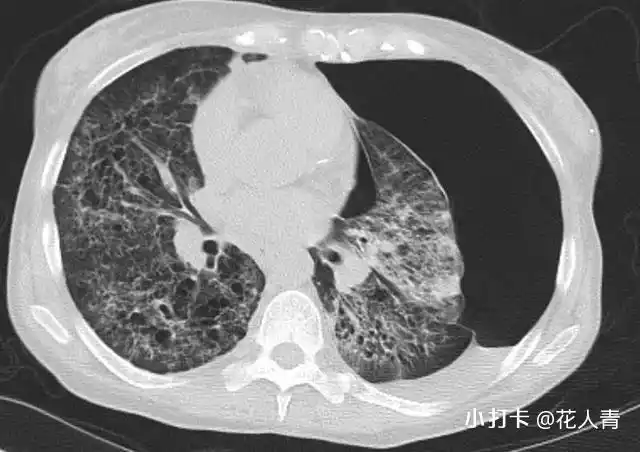

读胸部影像片,这 10 个特征性改变不可不知

胸片示弥漫性对称性网点状间质性阴影,伴左侧自发性气胸.